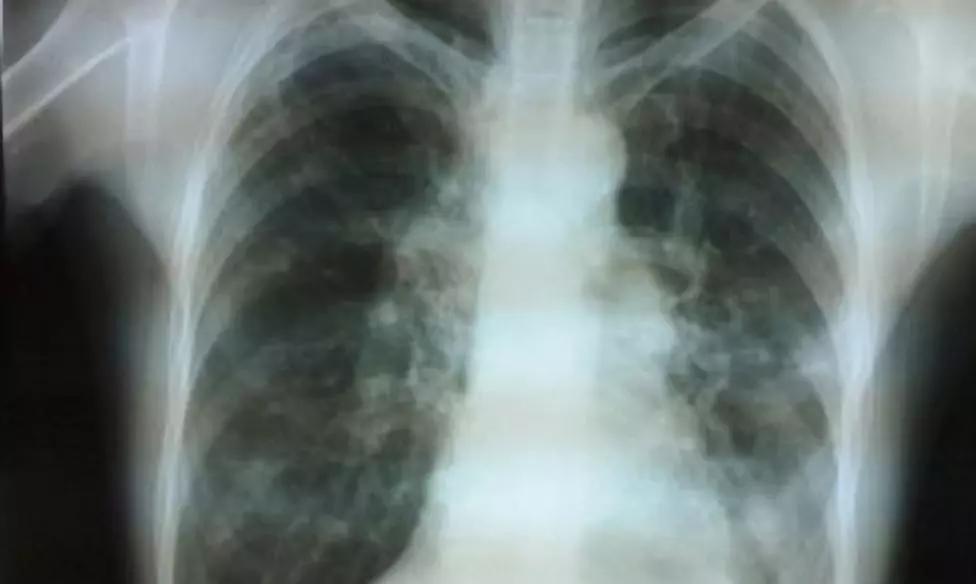

慢性支气管炎蔓延至支气管周围肺组织中就会发生支气管肺炎,这时患者寒战、发热、咳嗽增剧,痰量增加且呈脓性等症状,化验检查可见血白血球总数及其中性白细胞升高,X线检查两下肺野有斑点或小片状阴影。

多发生于儿童或青年期,常继发于麻疹、肺炎,有反复大量脓痰和咯血症状。两肺下部可听到湿罗音。胸部X线检查两肺下部支气管阴影增深,病变严重者可见卷发状阴影。

由于肺郁血而引起的咳嗽,常为干咳,痰量不多。详细询问病史可发现有心悸、气急、下肢浮肿等心脏病征象。体征、X线和心电图检查均有助于鉴别。

多发生在40岁以上男性,长期吸烟者,常有痰中带血,刺激性咳嗽。胸部X线检查肺部有块影或阻塞性肺炎。痰脱落细胞或纤维支气管镜检查可明确诊断。